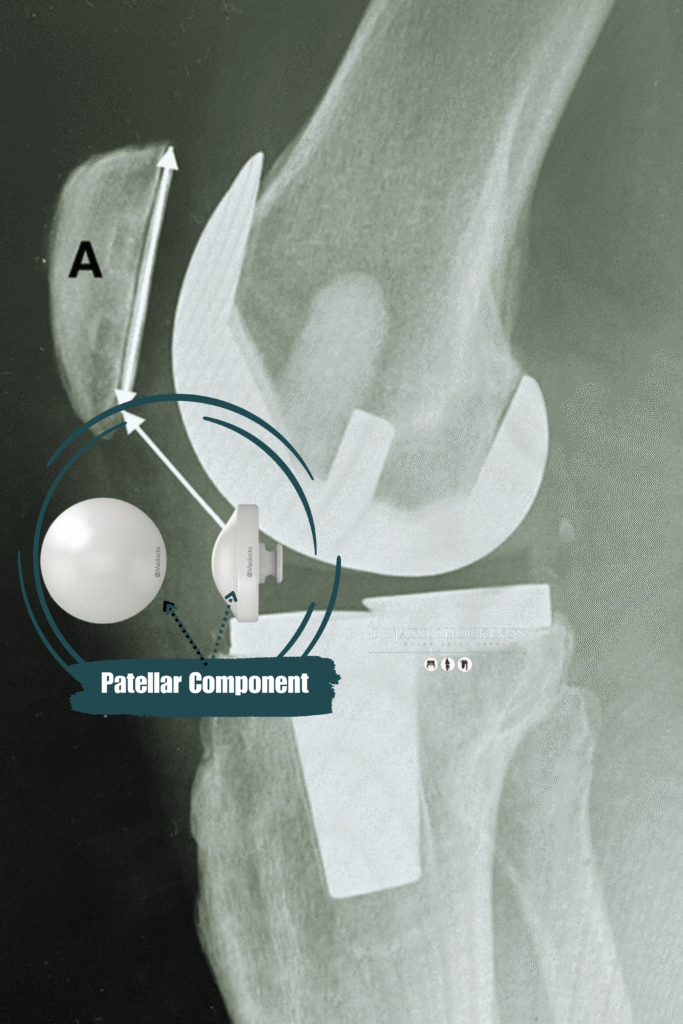

A total knee replacement typically involves three main components:

A metal cap that covers the end of the thigh bone (femur). This part is shaped to allow smooth bending and flexing of the knee.

A metal baseplate that sits on the top of the shin bone (tibia), often with a polyethylene (plastic) insert that serves as the new weight-bearing surface.

A plastic button that may be attached to the underside of the kneecap (patella), depending on the degree of wear and the condition of your natural cartilage.